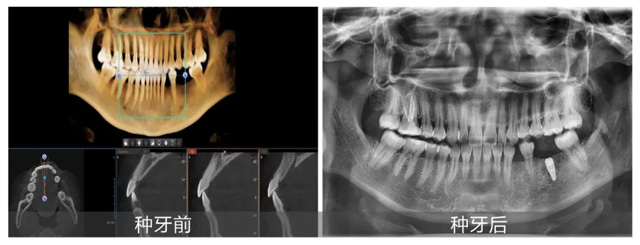

陆女士术前术后拍片对比

结合术后拍片结果,吴建方医生对本次手术进行了简单总结,现场观众们也纷纷利用和大咖面对面的机会,提出自己的疑问:“半口种牙需要多久?”“种植牙是一劳永逸的吗?”吴医生一一做了回答并表示:“非常高兴能通过手术直播和答疑的方式,帮助顾客朋友们了解种植牙,这也促进了我和大家的充分了解与信任。希望大家都能用最适合自己的方式,重拾好口福!”